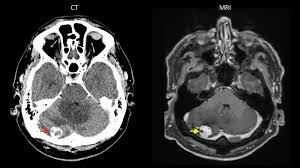

Eine der häufigsten Krebsarten in Deutschland ist LungenkrebsLebenserwartung und Heilungschancen hängen vor allem davon ab zu welcher Art der Tumor gehört und wie weit fortgeschritten er ist. Vor allem bei Metastasen sollte vor dem Versuch einer operativen. Es wurde im Kopf nur eine einzige Metastase gefunden was die Prognose im Gegensatz zu multiplen Metastasen verbessert.

Lebenserwartung und Heilungschancen Das Auftreten einer Hirnmetastase bedeutet dass sich der Primärtumor bereits weiter ausgebreitet hat. Auch ihre Seite sollten sie mal überarbeiten was heißt die Lebenserwartung bei Hirnmetastasen beträgt ein paar Wochen. Bei sehr vielen Metastasen oder Metastasen in der Hirnhaut liegt die Lebenserwartung jedoch nur bei wenigen Monaten.

Ursachen Diagnose Lebenserwartung. Was ist das für ein Blödsinn. Die medianen Überlebenszeiten die durch beide Therapieformen bei einzelnen und multiplen Metastasen erzielt werden sind vergleichbar und liegen zwischen sechs Monaten und einem Jahr sofern die Selektionskriterien berücksichtigt werden 13 - 15.

Wenn sich der Primärtumor gut behandeln lässt verbessert das die Chancen des Betroffenen. Meine Mutter hat Lungenkrebs mit Metastasen im Kopf. Wenn sich der Primärtumor gut behandeln lässt verbessert das die Chancen des Betroffenen. Ist das ursächliche Krebsleiden gut behandelbar überleben die. Auch ihre Seite sollten sie mal überarbeiten was heißt die Lebenserwartung bei Hirnmetastasen beträgt ein paar Wochen. Deshalb konnte deine Mutter auch operiert werden. Es wurde im Kopf nur eine einzige Metastase gefunden was die Prognose im Gegensatz zu multiplen Metastasen verbessert. Es gibt die Ganzkopfbestrahlung und dann gibts immerhin noch das Gamma knife. Mit der richtigen Behandlung lässt sich aber die Lebenszeit vieler Patienten zumindest verlängern.